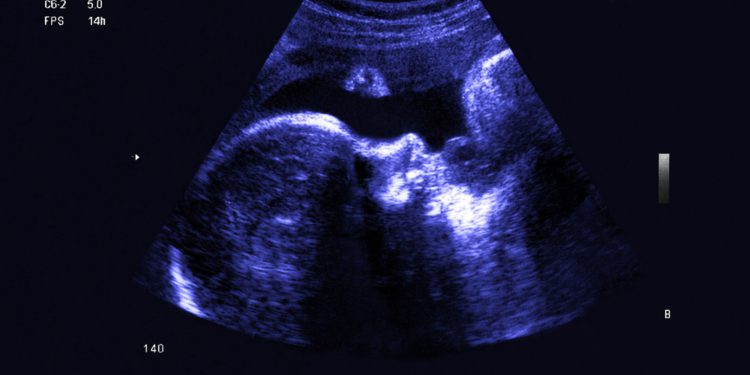

Современная технология и медицина позволяют заглянуть в чрево матери и в реальном времени увидеть, что происходит с младенцами до рождения: как они двигаются, растут и меняются. Просто удивительно!

На видео показано, как на четвертой неделе бьется сердце младенца — спустя всего лишь неделю после того, как оно вообще начало биться.